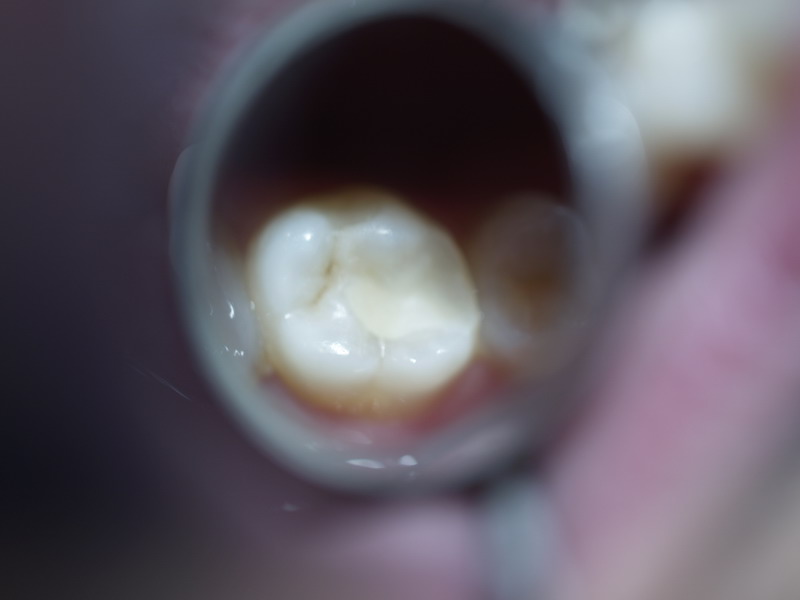

Clinical Evaluation Of Dental Restorative Materials . Recommendations for conducting controlled clinical studies of dental restorative materials. To evaluate class v cavities restored by different bioactive restorative materials. The ranking of restorative materials used in clinical practice showed a better performance of gic for the control of sc in. About 35 years ago, ryge provided a. Since untreated dental caries remain a worldwide burden, this umbrella review aimed to assess the quality of evidence on the clinical effectiveness. The criteria for the evaluation of dental restorative materials presented in this report have been designed to measure clinically important. The authors outlined the potential of the criteria to be applied 1) in evaluations of new restorative materials or operative techniques in clinical. Rating scales were developed for several factors that were considered relevant to the problem of clinically evaluating dental.